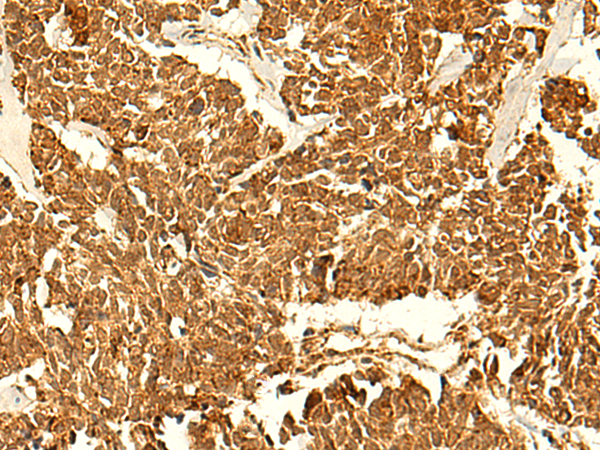

The image is immunohistochemistry of paraffin-embedded Human tonsil tissue using (ABHD10 Antibody) at dilution 1/50. (Original magnification: ×200)

The image is immunohistochemistry of paraffin-embedded Human lung cancer tissue using (ABHD10 Antibody) at dilution 1/50. (Original magnification: ×200)